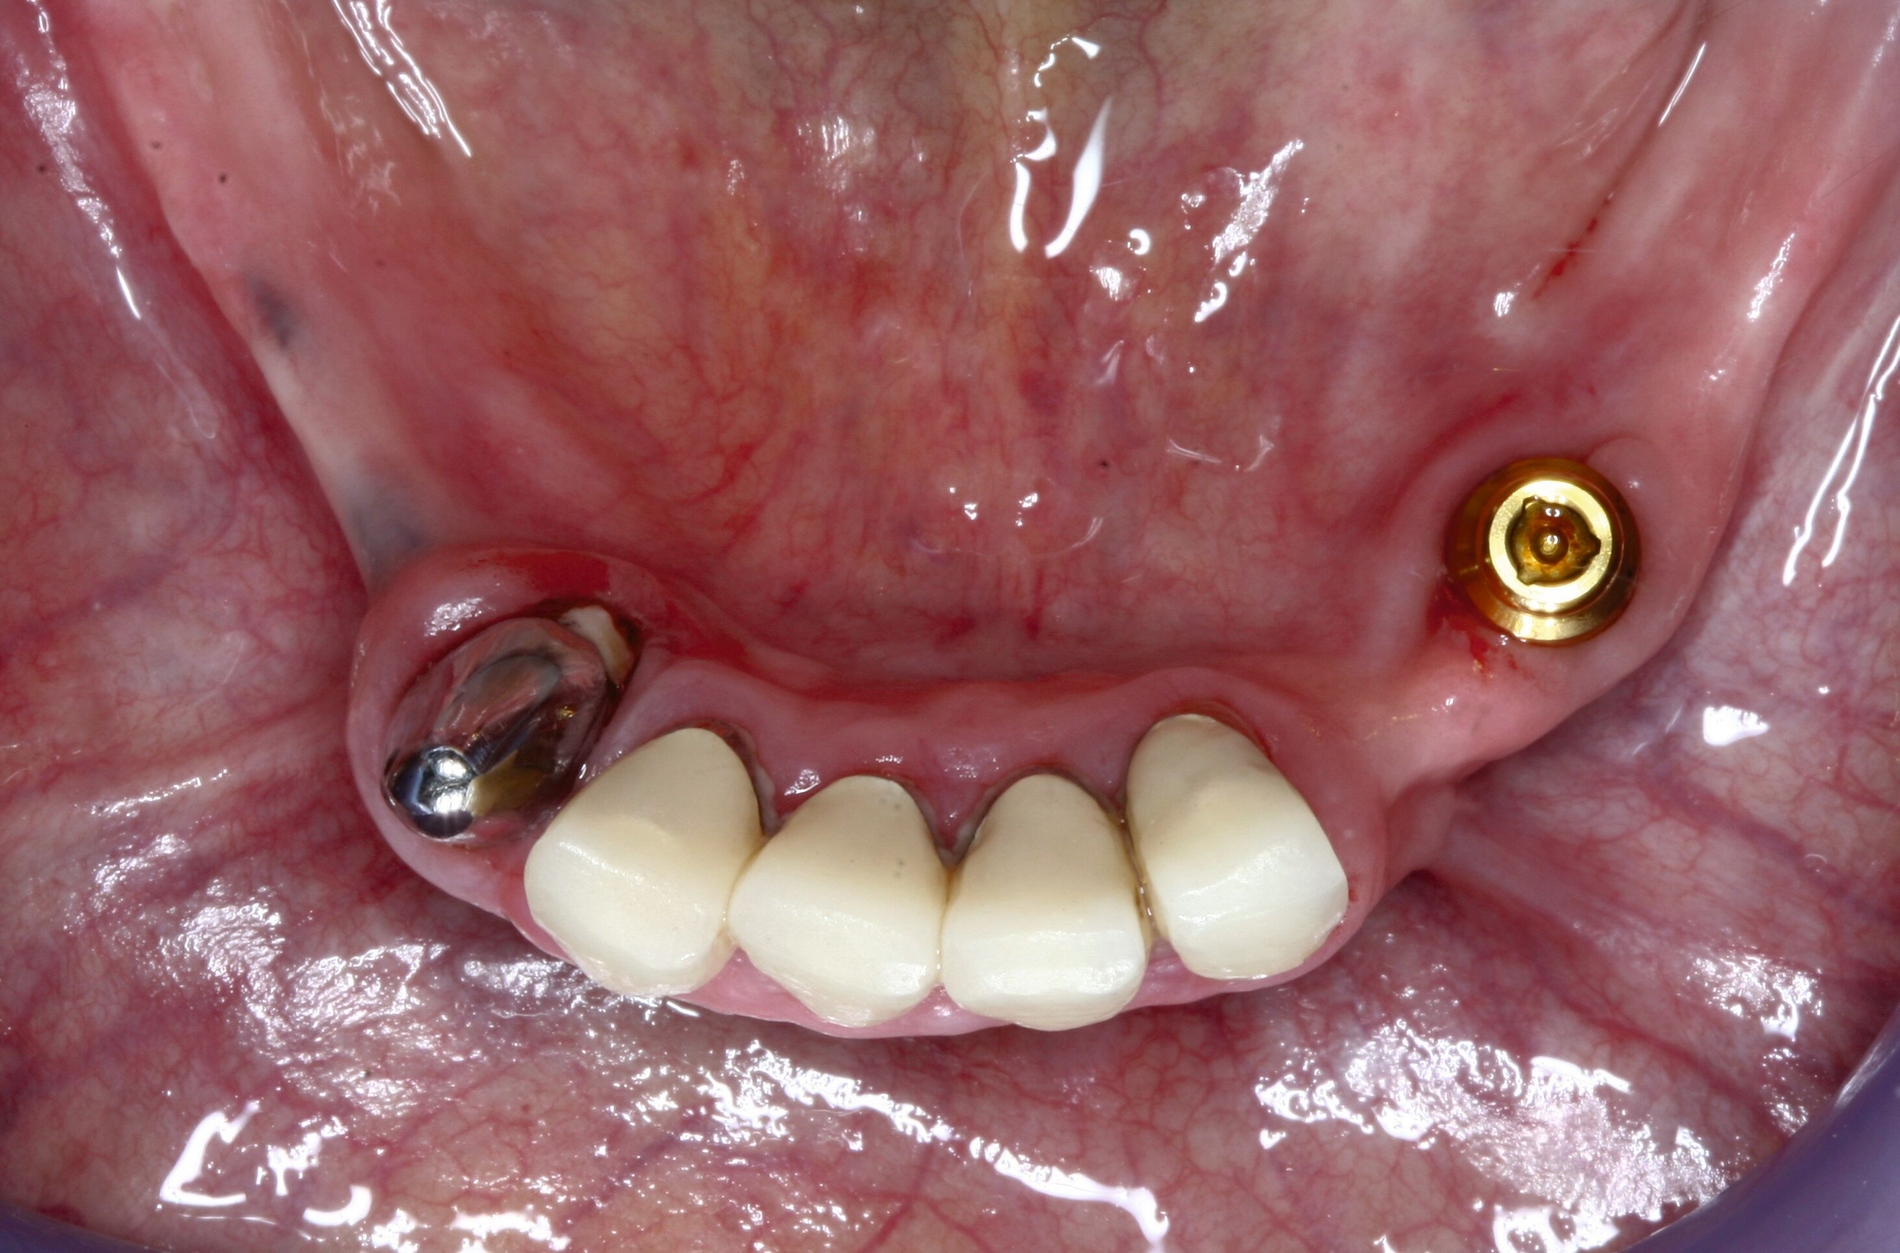

Sind größere Veränderungen am Zahnersatz erforderlich, so gilt es zu beachten, dass dieser zusammen mit der Zunge und der Wange einen fein abgestimmten Regelkreis fürs Kauen, Sprechen und Schlucken bildet. Bei Formveränderungen am Zahnersatz muss sich dieser Regelkreis neu programmieren – doch mit zunehmender Alterung nimmt diese Fähigkeit ab. Verbliebene wiedererkannte Konturen können helfen, die Adaptation an den umgestalteten Zahnersatz zu erleichtern. Es hat sich deshalb bewährt bei größeren Veränderungen des Mundraums, beispielsweise nach mehrfachem Zahnverlust, den bestehenden Zahnersatz eher umzuarbeiten, anstatt neu zu konstruieren. Im folgenden Beispiel wurden diese Überlegungen umgesetzt (Abbildung 8).

Der Verlust eines prothesendynamisch relevanten Pfeilerzahns konnte durch den größeren Abstand zur Doppelkrone mithilfe eines Locators ausgeglichen werden. Das Implantat wurde interforaminär an der Position 44 simultan zur Extraktion des Zahnes 43 gesetzt. Die Prothese musste anschließend nur unterfüttert und die Locatormatrize einpolymerisiert werden. Die Behandlung konnte so mit einer Mindestzahl an notwendigen Behandlungsterminen durchgeführt werden (Abbildung 8).